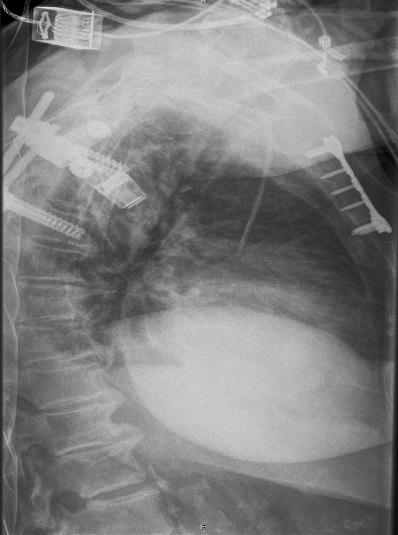

Fall from 4-meter height

Mechanism of injury: An 81 year old woman fell onto her back from a height of 4 meters. (Fig 6a-d) She sustained a multiple sternal fracture concomitant with a fracture of the 5th thoracic vertebra resulting in an unstable injury of the trunk. Fortunately she did not show any neurologic deficit or paraplegia.

Diagnosis: Complex sternal fracture with multidirectional instability (longitudinal fracture of the manubrium, transverse fracture involving 3 levels of manubrium and corpus sterni) Concomitant to this was a fracture of the 5th thoracic vertebra (AOB2.1).

Treatment: The sternal fracture has been managed by open-reduction and internal fixation with a locked plate osteosynthesis (MatrixRIB, I-Plate) through an anterior approach in the mid-line. b The thoracic spine has been managed employing dorsal instrumentation (internal fixator th4-th6).

Post-operative outcome: The wounds and bone healed uneventfully. Breathing was possible spontaneously without any restrictions. The patient reported on a significant reduction of the pain immediately after the operative procedure. Mobilization on the ward started on the first day after the procedure. No complications such as secondary failure, non-unions, pain or deformity of the chest wall could be seen during the follow up examinations of 6 and 12 weeks and 6 and 12 months.